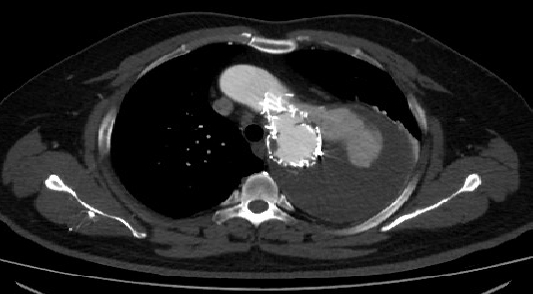

男性,44岁,慢性B型夹层。2010年12月行TEVAR术。

2013年5月发现RTAD,未处理。2015年2月死亡。